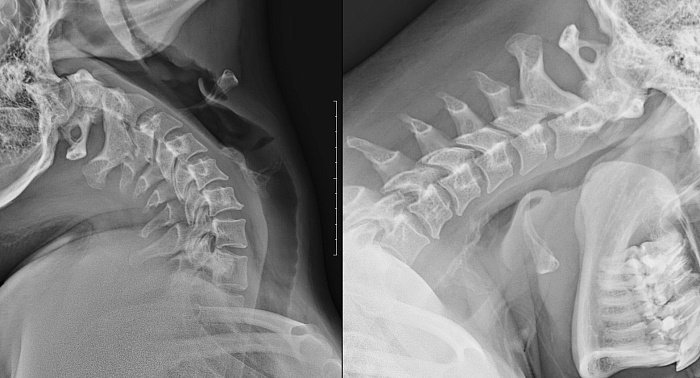

Рентгенография одного отдела позвоночника: функциональные пробы – важный метод скринингового исследования, который позволяет оценить состояние отдела позвоночника.

Диагностическая услуга выполняется в двух проекциях.